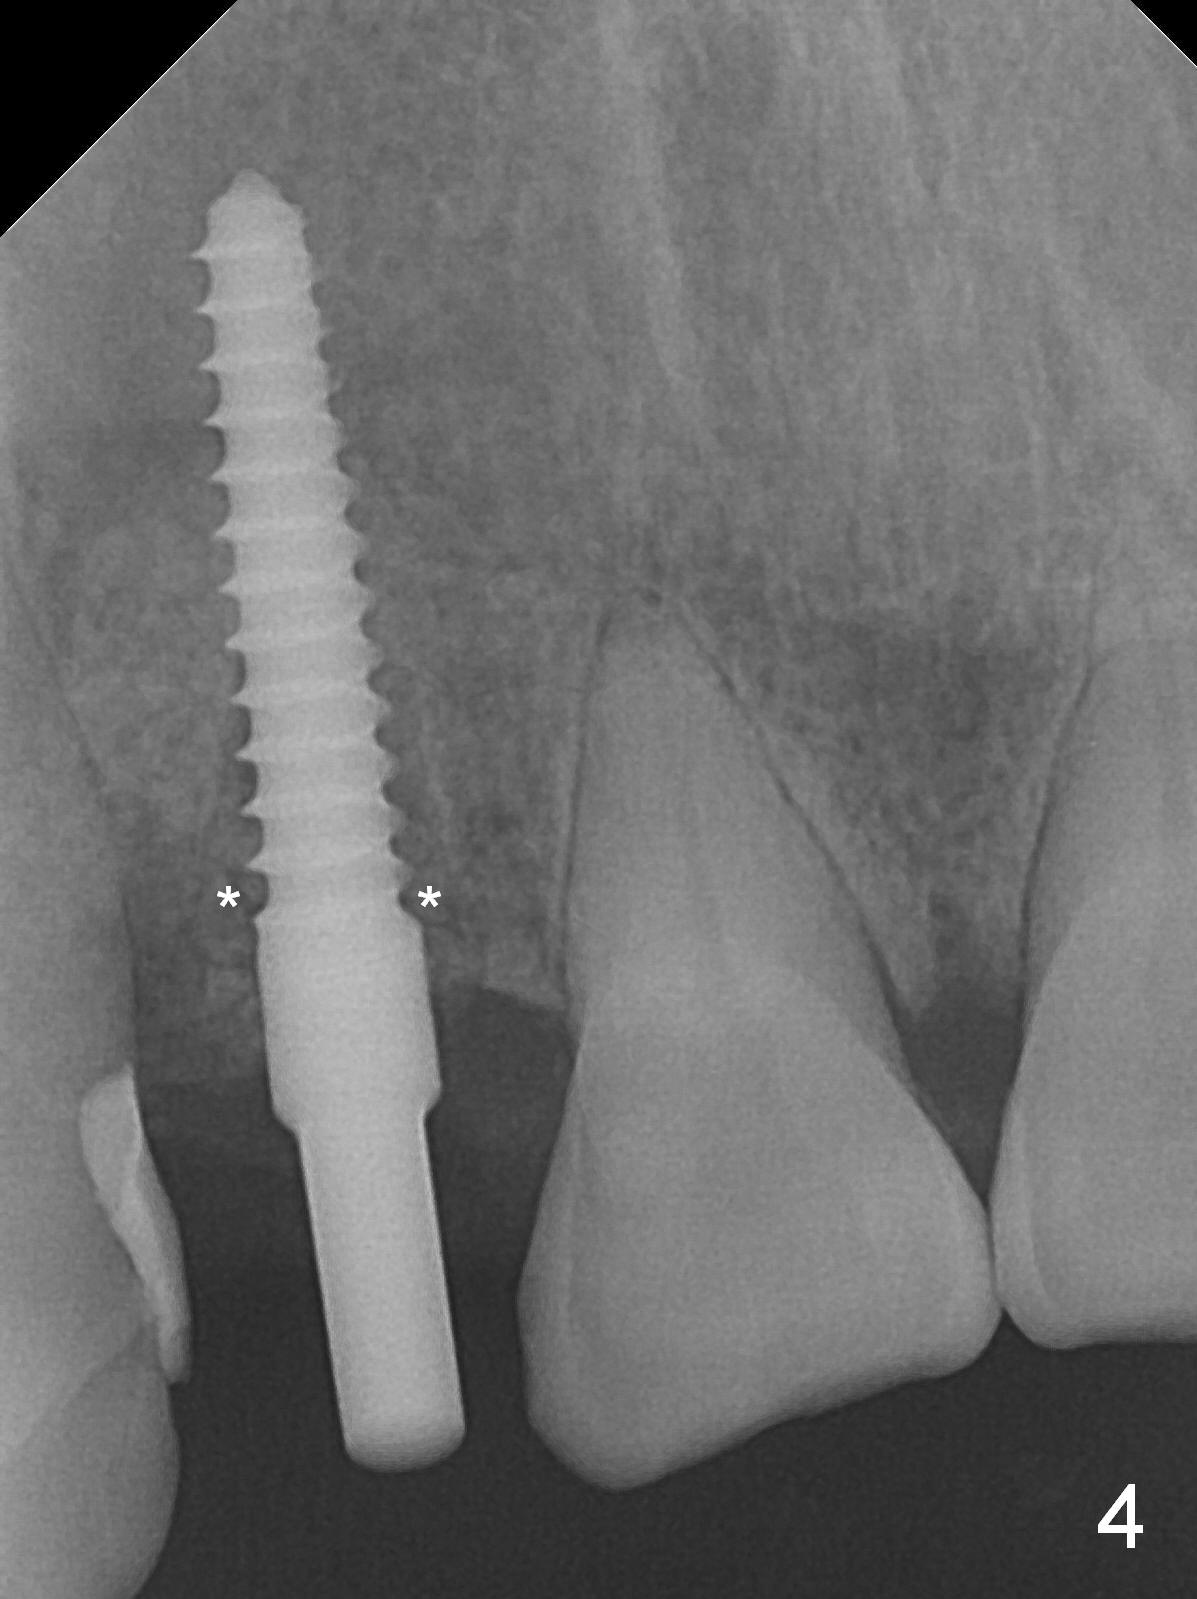

When the flaps are raised, the buccal plate is found to be perforated (Fig.2 *); osteotomy is being established in the narrow palatal wall (<). When a 3x17 mm (tissue-level) 15 ° 1-piece implant is placed (Fig.3,5 P), the incisal end of the implant is between the incisal edge of the central incisors and that of the tooth #10 (Fig.6) so that the temporary crown (Fig.7 T) is slightly buccal with sufficient palatal clearance with the opposing dentition.

Sixteen days postop, the patient is doing fine, although the labial fistula has not disappeared (Fig.8 <). The detached distolabial papilla is healing (Fig.9 *) with mild bone graft exposure (^). The lacerated distopalatal papilla is also healing (Fig.10 *). These complications are related to flap surgery. The apical portion of the socket appears to have reduced 4 months postop (Fig.14). When the definitive restoration is delivered 5 months postop, there is gingival recession, including the distal of #8 (Fig.11 arrows, which is expected to improve over time) due to flap surgery. The labial plate collapse is minimal (Fig.12 *), while the palatal laceration (Fig.10) has healed (Fig.13). When the patient returns 1.5 years post cementation, there is increased bone density next to the coronal portion of the implant, equivalent to the bone graft (Fig.15 *). The fistula is absent (Fig.16). The crestal bone loss remains 2.5 years post cementation (Fig.17 *), although there is no sign of periimplantitis (magnification). Oral hygiene is poor. There is no change in the soft (gingival recession; data not shown) or hard tissues 3 years 8 months post cementation (Fig.18).